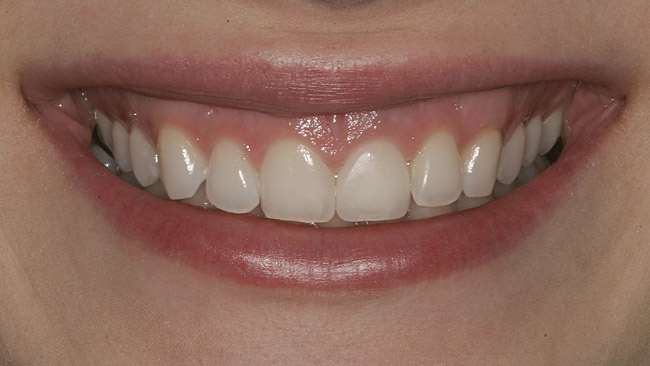

Figure 23  Final zirconia crown, No. 9—full-smile view.

Figure 23

The final screw-retained crown was delivered and torqued onto the implant to 35 Ncm; the restorative dentist then sealed the screw access with a cotton pellet and composite (Figure 20 and Figure 21). Various views of the final crown are shown in Figure 22 through Figure 25, including a full-face photograph.

The patient, who works as a professional model, was pleased with her esthetic result, which was a paramount criterion for the team approach applied to this case, as emphasized by Vermylen et al, who reported positive to very positive ratings on esthetics and phonetics among 48 patients with 52 implants on which crowns were fabricated by their restorative dentists.12

This patient faced a unique situation, perhaps not previously reported: retaining a healthy mandibular lateral incisor knowing this would create an esthetic compromise. Indeed, while the discrepancy in gingival-margin height is noticeable in retracted view (Figure 7), it does not show in full smile (Figure 8).

Figure 8  Full smile—finished feldspathic crowns on teeth Nos. 22, 23, 27, and 28; implant crowns in sites 24 through 26; esthetic harmonization with opposing dentition.

Figure 8